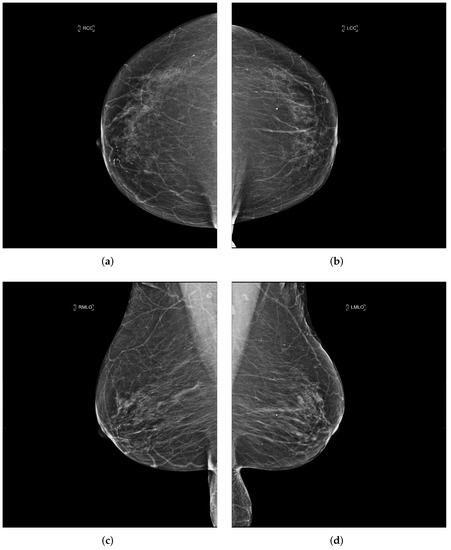

Each performed mammography exam includes four standard views: a CC and a MLO view for each, the right and left breast, as illustrated in Figure 3.

Figure 3. Example of a mammography study selected from the collected dataset showing the four standard views (ad). (a) right cranio-caudal (R-CC); (b) left cranio-caudal (L-CC); (c) right mediolateral oblique (R-MLO); (d) left mediolateral oblique (L-MLO).